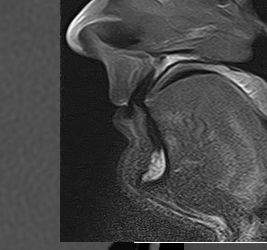

Radiologie - Echographie - Mammographie - Scanner - IRM

Scanner, IRM, échographie, radiographie... Injection d'iode, de gadolinium...